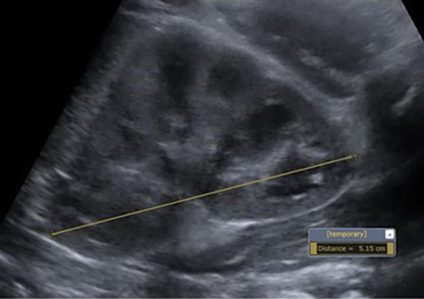

Urolithiasis: An 8-mm partially obstructed proximal left ureteral stone.